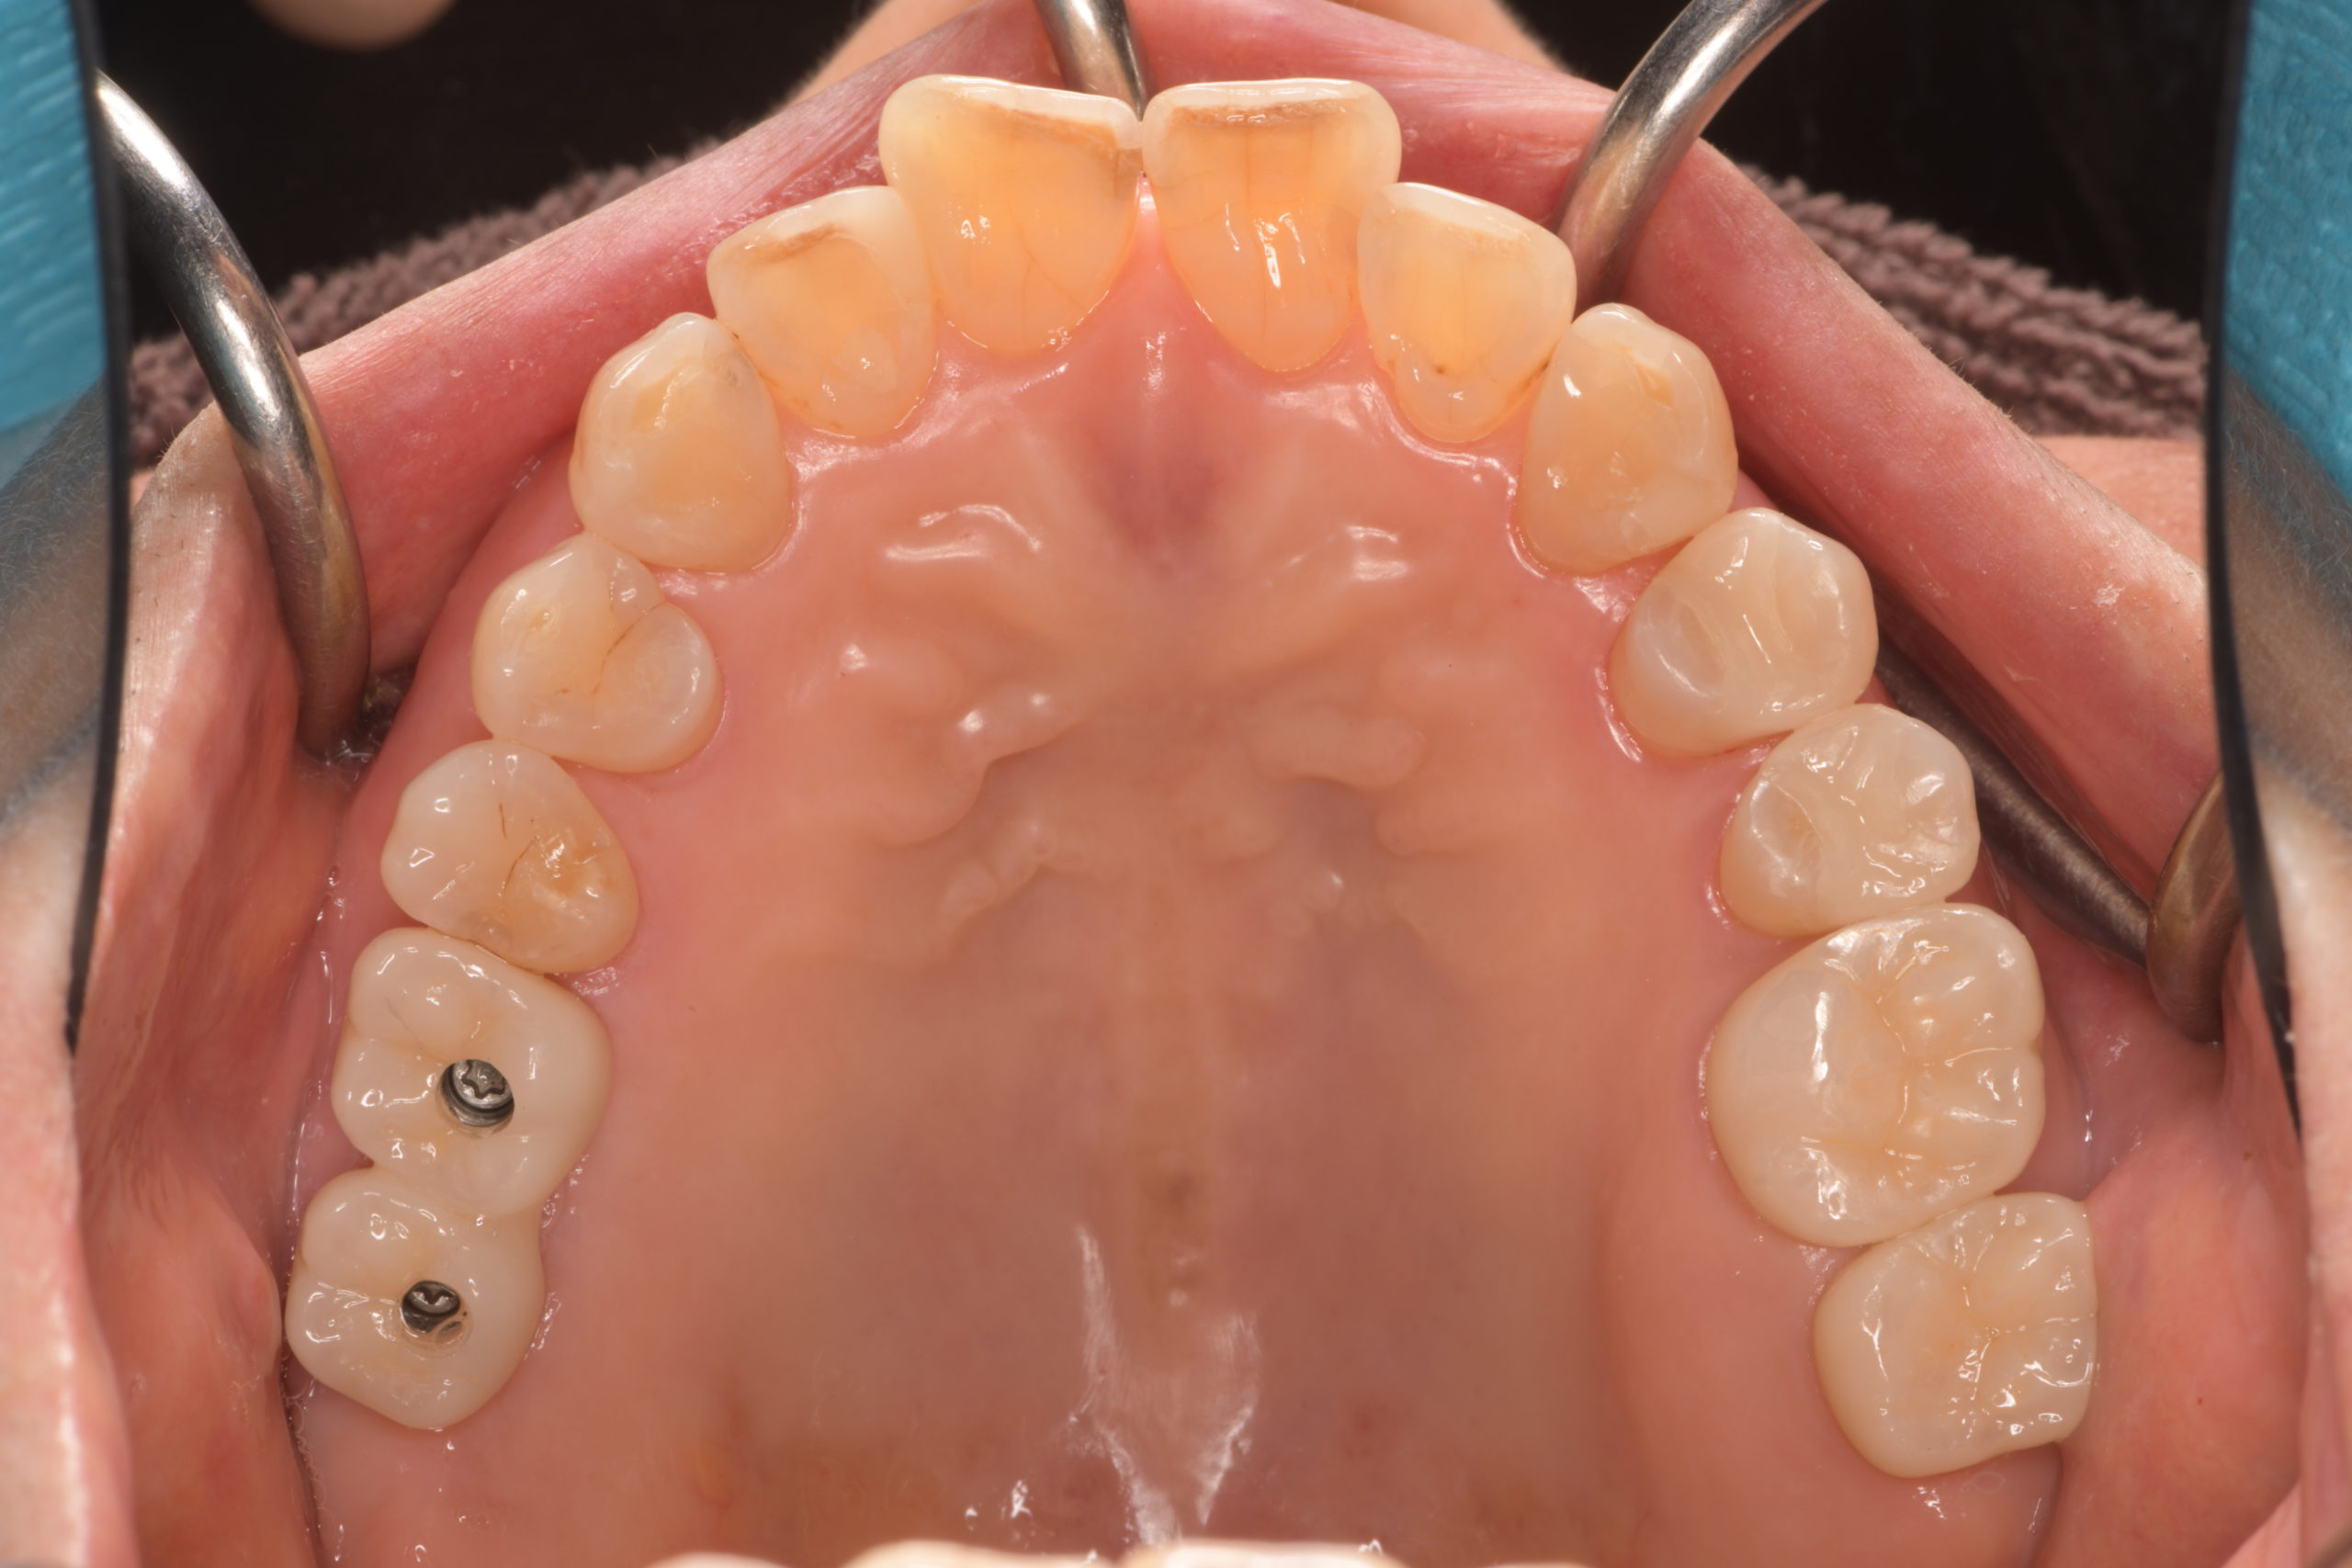

上顎臼歯部インプラント治療前

上顎臼歯部インプラント上部構造装着前

上顎臼歯部インプラント治療完了